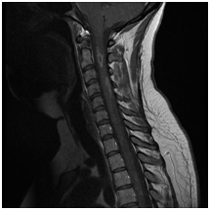

Anatómiai nyaki gerinc, láthatóvá MRI.

MRI lehetővé teszi, hogy megjelenítsék morfológiai változások: a csigolyatestek, porckorongok, gerincvelő, dura térben, az ideg gyökerek környező paravertebralis lágyrész, érrendszeri szerkezetek, amelyek a kutatási területen.

A módszertan az eljárás, mágneses rezonancia képalkotás a nyaki gerinc.

A szklerózis multiplex. Foci demielinálódás a gerincvelőben.

Syringomyelic ciszta gerincvelő

Veleszületett rendellenességek: hipoplázia szervek C5, C6, C7 csigolyák; részleges konkrestsentsiya (fúziós) tel C5-C7 csigolyák.